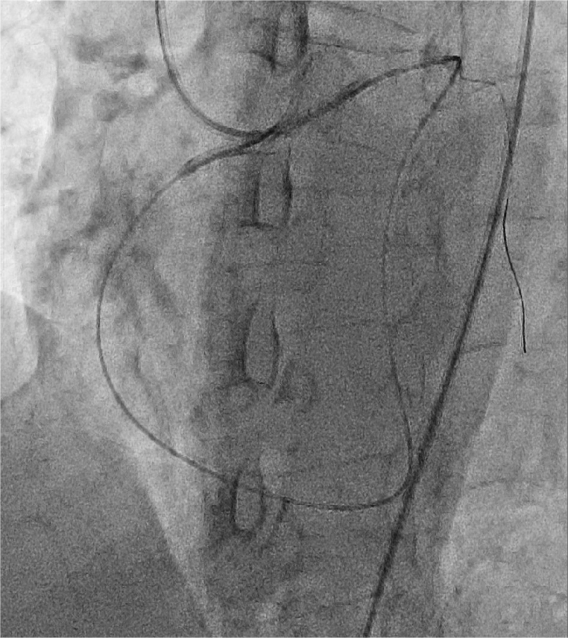

4月24日,朱舜明副主任医师为患者制定周密的手术方案和风险处理方案,朱舜明副主任医师、唐治国主治医师、张翔主治医师、张豪住院医师开展持续3小时的介入手术。术中穿刺桡动脉和股动脉,双路径同时造影显示病变血管完整结构,开展Reverse-CART技术,将逆向导丝送入正向指引导管,跟进微导管,交换导丝后用球囊扩张病变,沿逆向导丝送入双腔微导管至闭塞血管远端,沿双腔微导管送入正向工作导丝至右冠后降支,并退出逆向微导管和导丝,采用血管内超声精细评估病变情况,最终向右冠状动脉内植入3枚支架。术后多体位造影未见残余狭窄及贴壁不良,完美结束手术。

图3 交换RG3导丝沿逆行血管路径通过病变部位